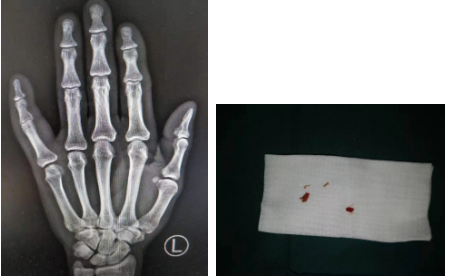

厉医生决定为李大爷行手术治疗,在完善了各项术前检查后,手术团队为其进行了左小指切开引流+异物取出术,术中探查见左小指指深、指浅屈肌腱部分变性坏死,屈肌腱下方有4块大小不一的木屑,正散状分布着,手术团队取出全部木屑,清除失活组织。手术非常顺利,1个小时左右就完成了。术后李大爷非常满意,对厉医生的医术表示赞叹!

厉医生介绍,木屑非常特殊,它拍片时不显示,所以无法单纯通过片子判断手指里面到底有没有异物。像其他异物如晶体硅片、铁屑,是可以探测出来的。而木屑在手指内部长时间存留,会造成肌腱感染、液化,导致手指坏死,面临截指风险。所以提醒大家,被异物刺伤之后,第一时间到专科医院就诊。